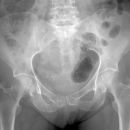

Coxarthrose